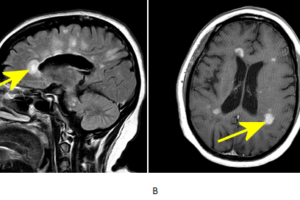

Dawson’s Fingers

Multiple sclerosis is the most common demyelinaing disease and the most common disabling CNS disease of young adults. The etiology is not certain but likely autoimmune. The disease is characterized by the... Read more »